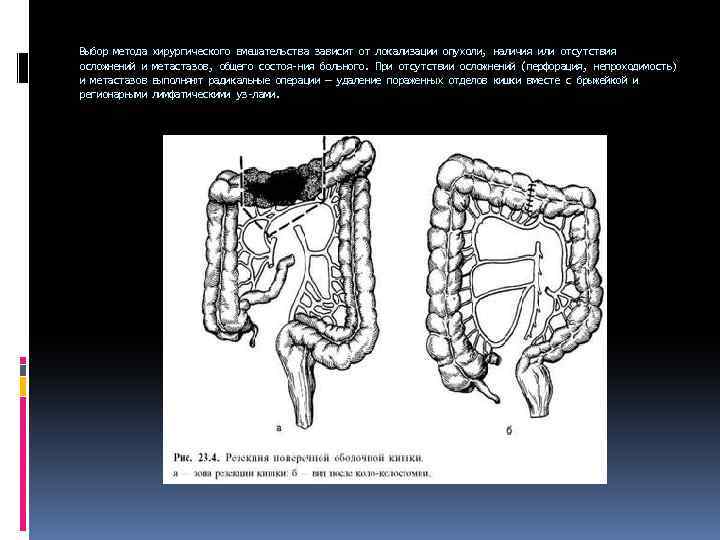

Выбор метода осложнений и и метастазов регионарными хирургического вмешательства зависит от локализации опухоли, наличия или отсутствия метастазов, общего состоя ния больного. При отсутствии осложнений (перфорация, непроходимость) выполняют радикальные операции — удаление пораженных отделов кишки вместе с брыжейкой и лимфатическими уз лами.